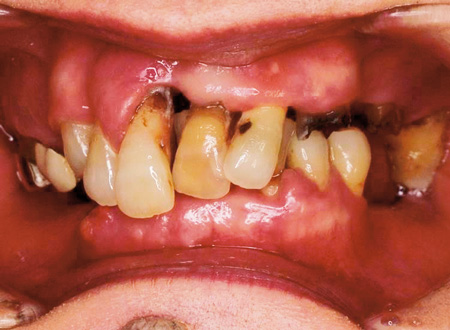

60代女性。虫歯と歯周病の進行があり、前歯が突出している。

左上の奥歯は歯の崩壊があり下の奥歯は喪失していることから、噛むところがなく食べることが困難になっていた。